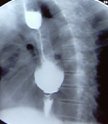

Postoperative barium esophagography. Smooth passage of contrast through the myotomy site (Courtesy Dr. V. Penopoulos)